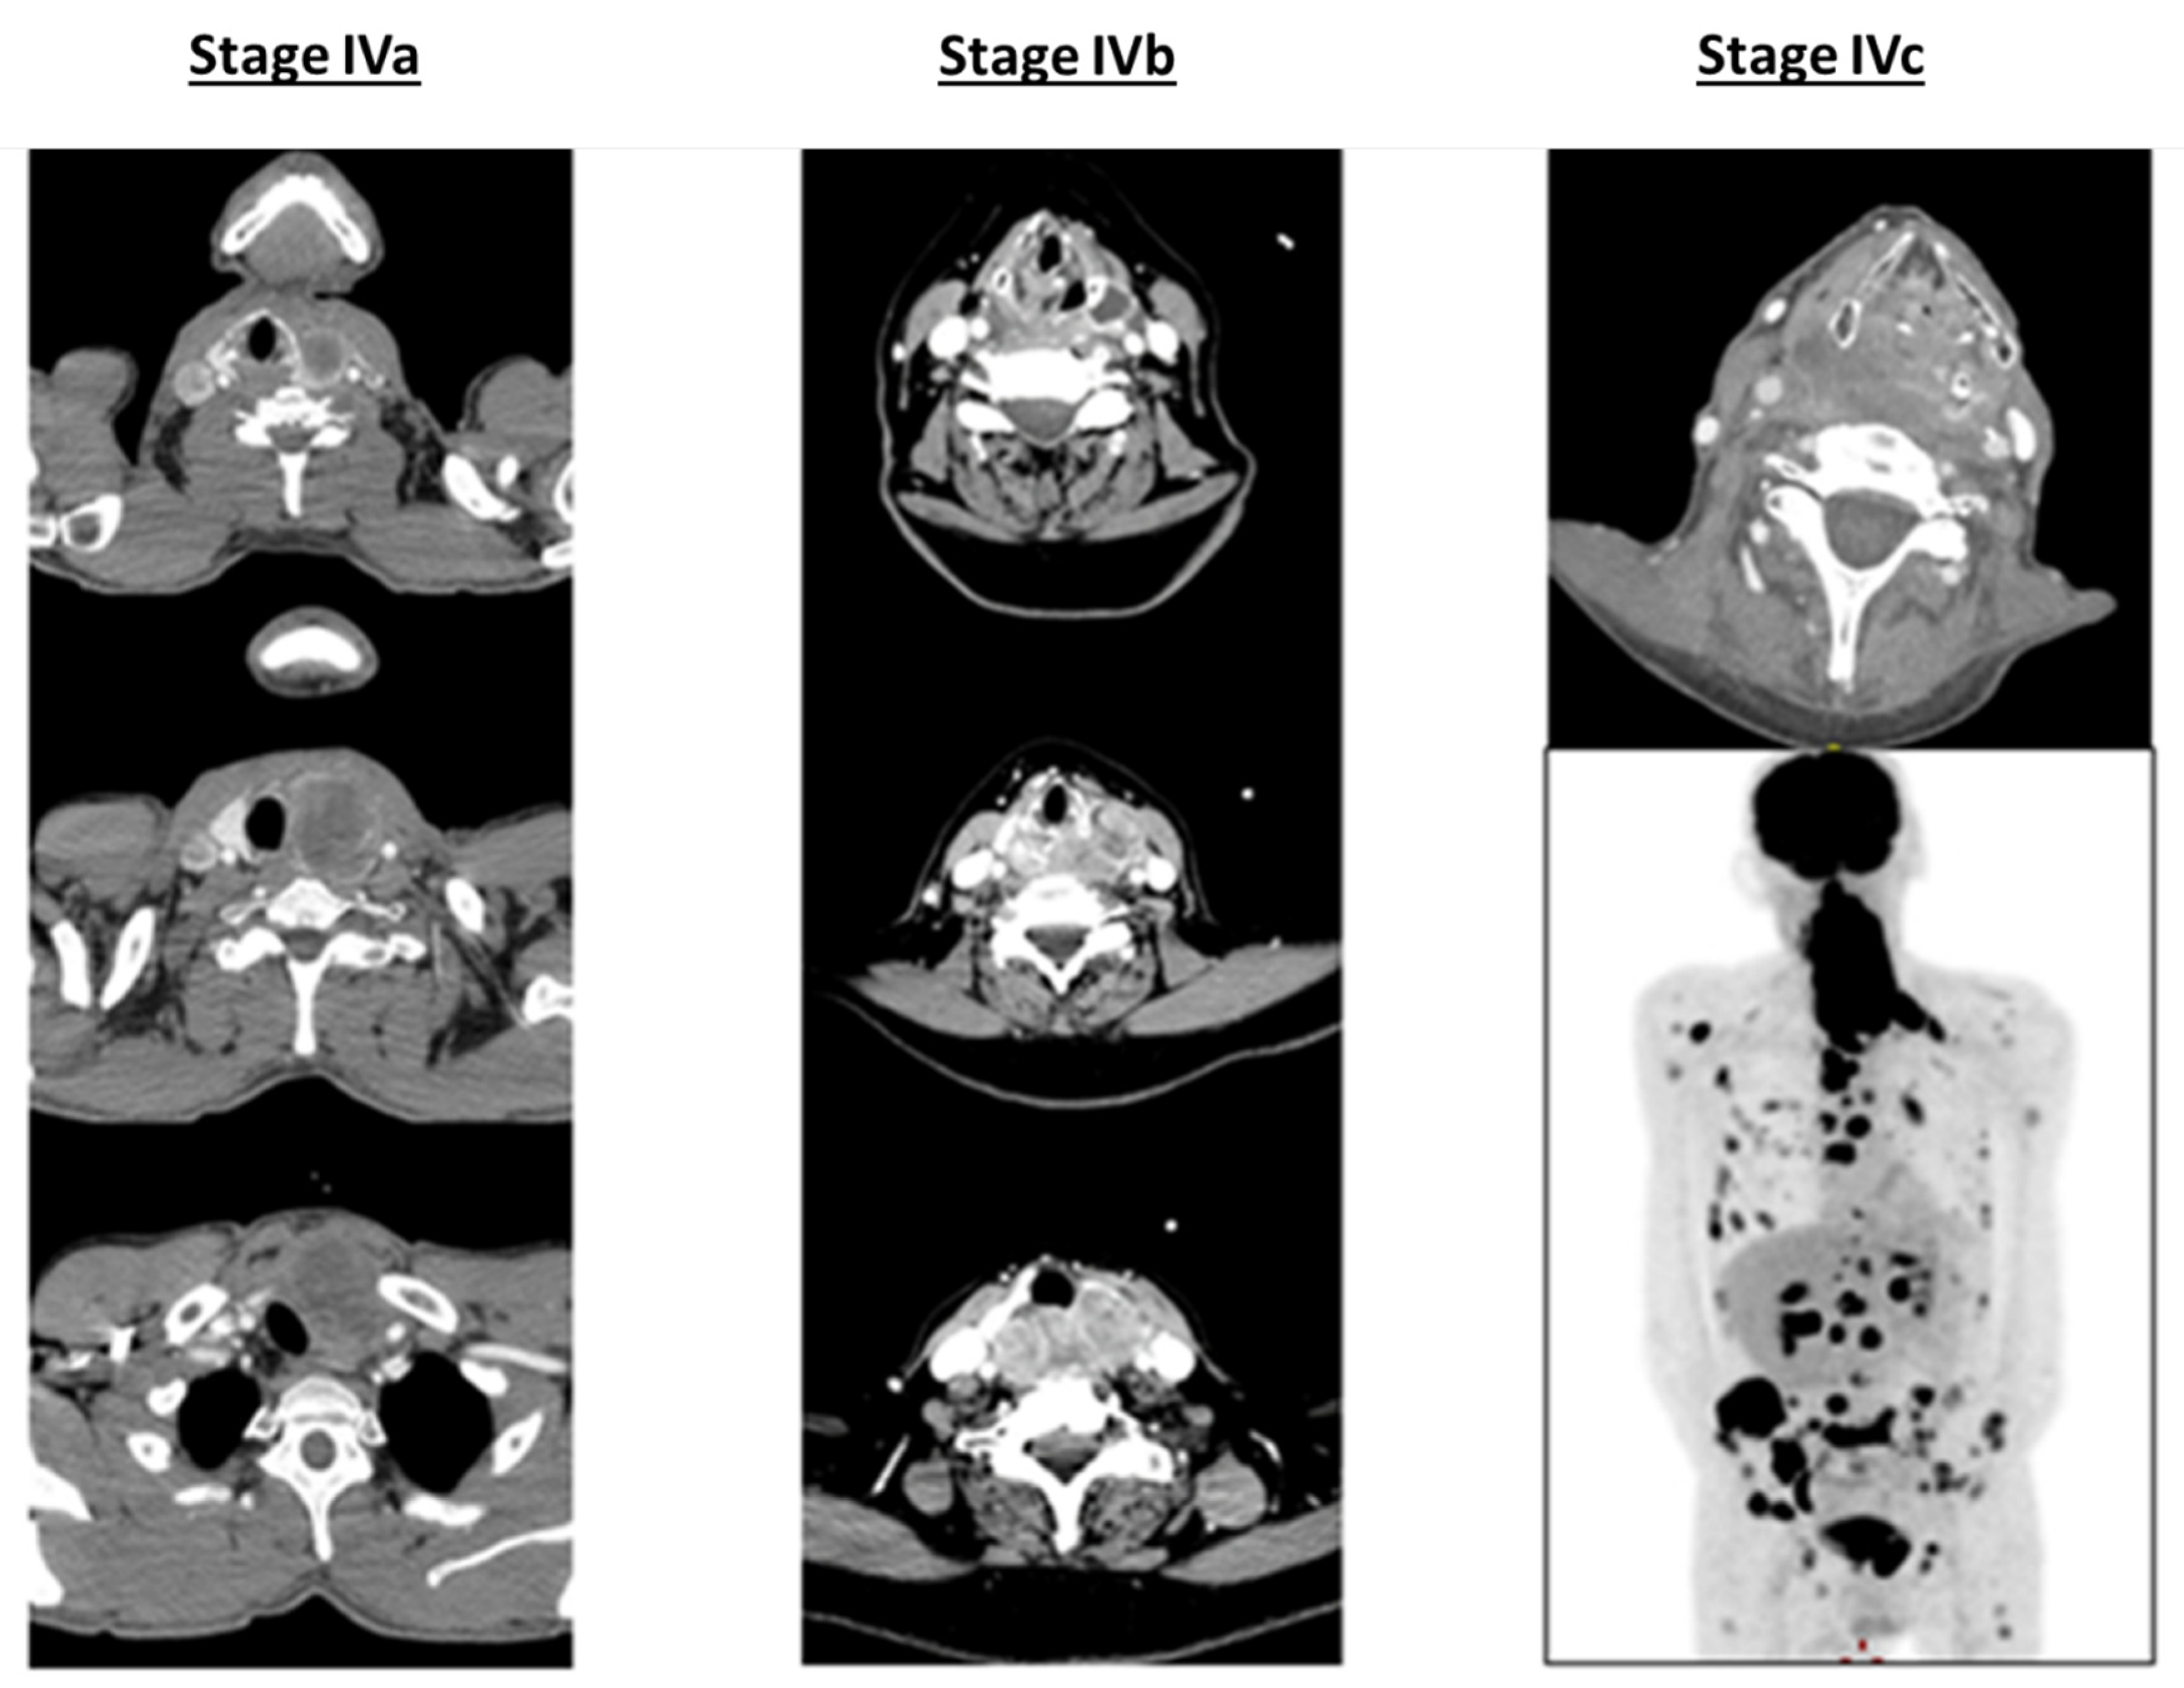

ATC usually affects elderly patients, with the majority being over 60 years old with a female predominance (male/female sex ratio = 1.5:2). The advanced stage of the disease is the most common diagnosis presentation (localized (IVa) 10%, locally advanced (IVb) 35% and metastatic (IVc) 55%) displaying extremely aggressive behavior with rapid tumor progression, local invasion and/or distant metastases (lung, bone, liver and/or brain metastases) [1,2,19,20,21] (Figure 1).

Figure 1.

CT scan illustration of anaplastic thyroid carcinoma (ATC) staging.